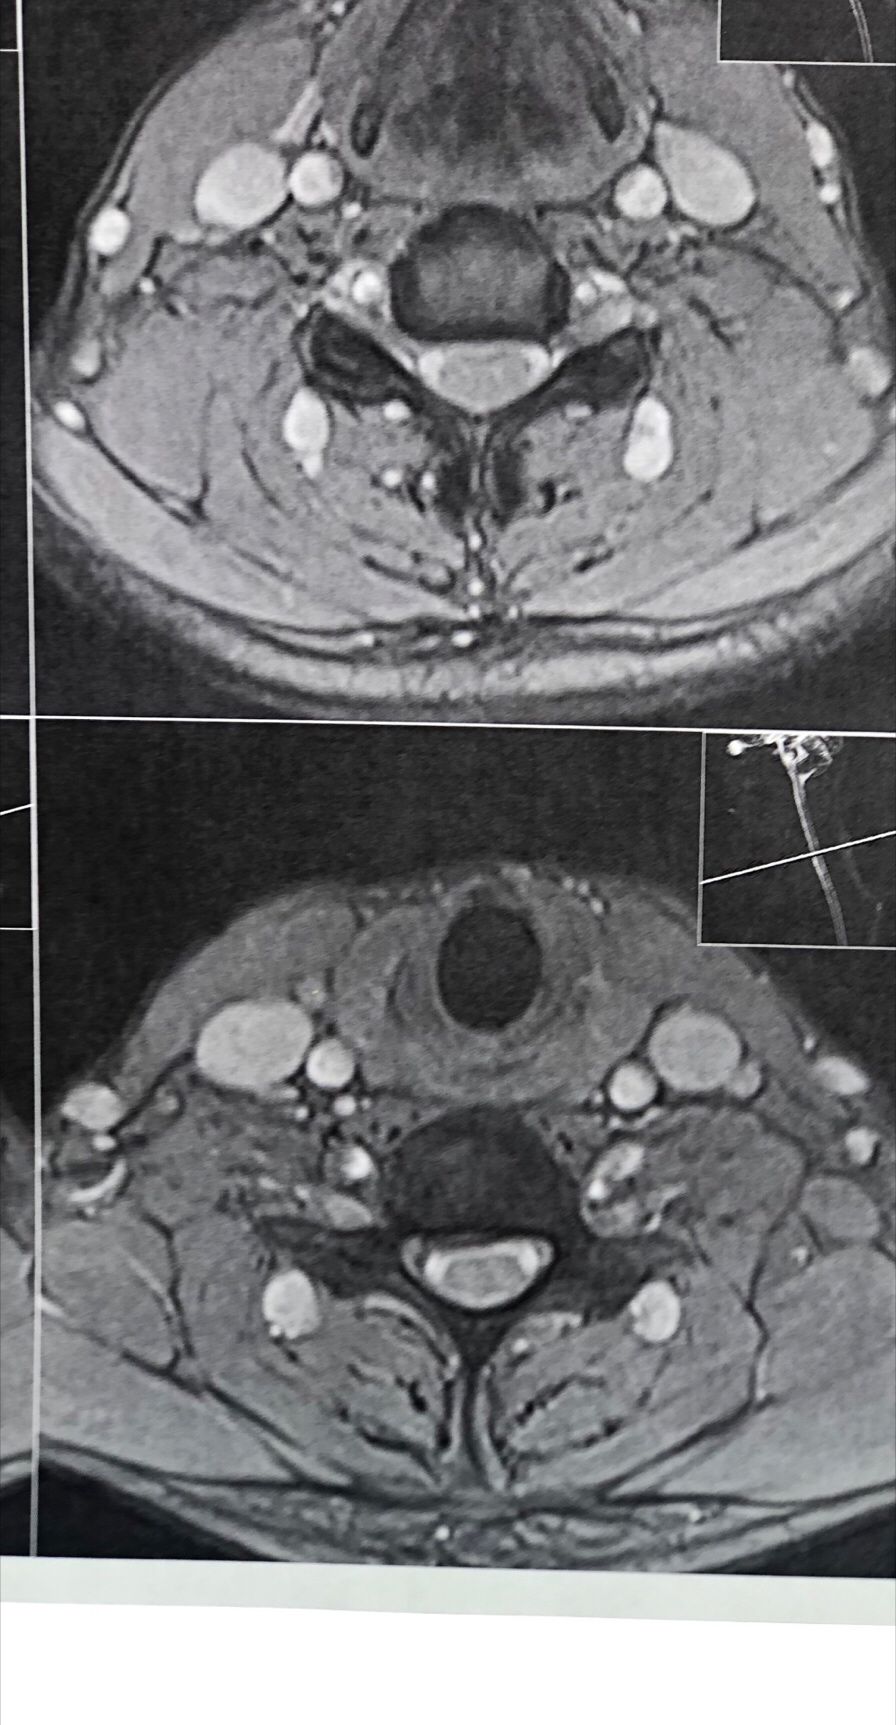

A 65-year-old patient presented to my office 20 days ago with right hip/gluteal pain, mainly occurring after walking approximately 200 meters. He also reported right shoulder and neck pain.

On examination, the right shoulder range of motion was normal. However, cervical spine (C/S) range of motion was severely restricted by about 80% in all directions. There was severe right C5–C7 dysfunction. Neurological examination revealed a positive right-sided Hoffman’s sign, unremarkable Babinski sign, and bilateral L4 deep tendon reflexes graded 1+. On palpation of the lumbar spine, step defects were noted. Right hip examination was otherwise normal.

Cervical and lumbar MRI, dynamic lumbosacral X-rays, and EMG/NCV of the lower limbs were ordered. The patient brought all results today (August 18, 2025).

Request:

Please review his MRI and X-ray findings. Based on these, what are your differential diagnoses, final diagnosis, and plan of management (POM)?